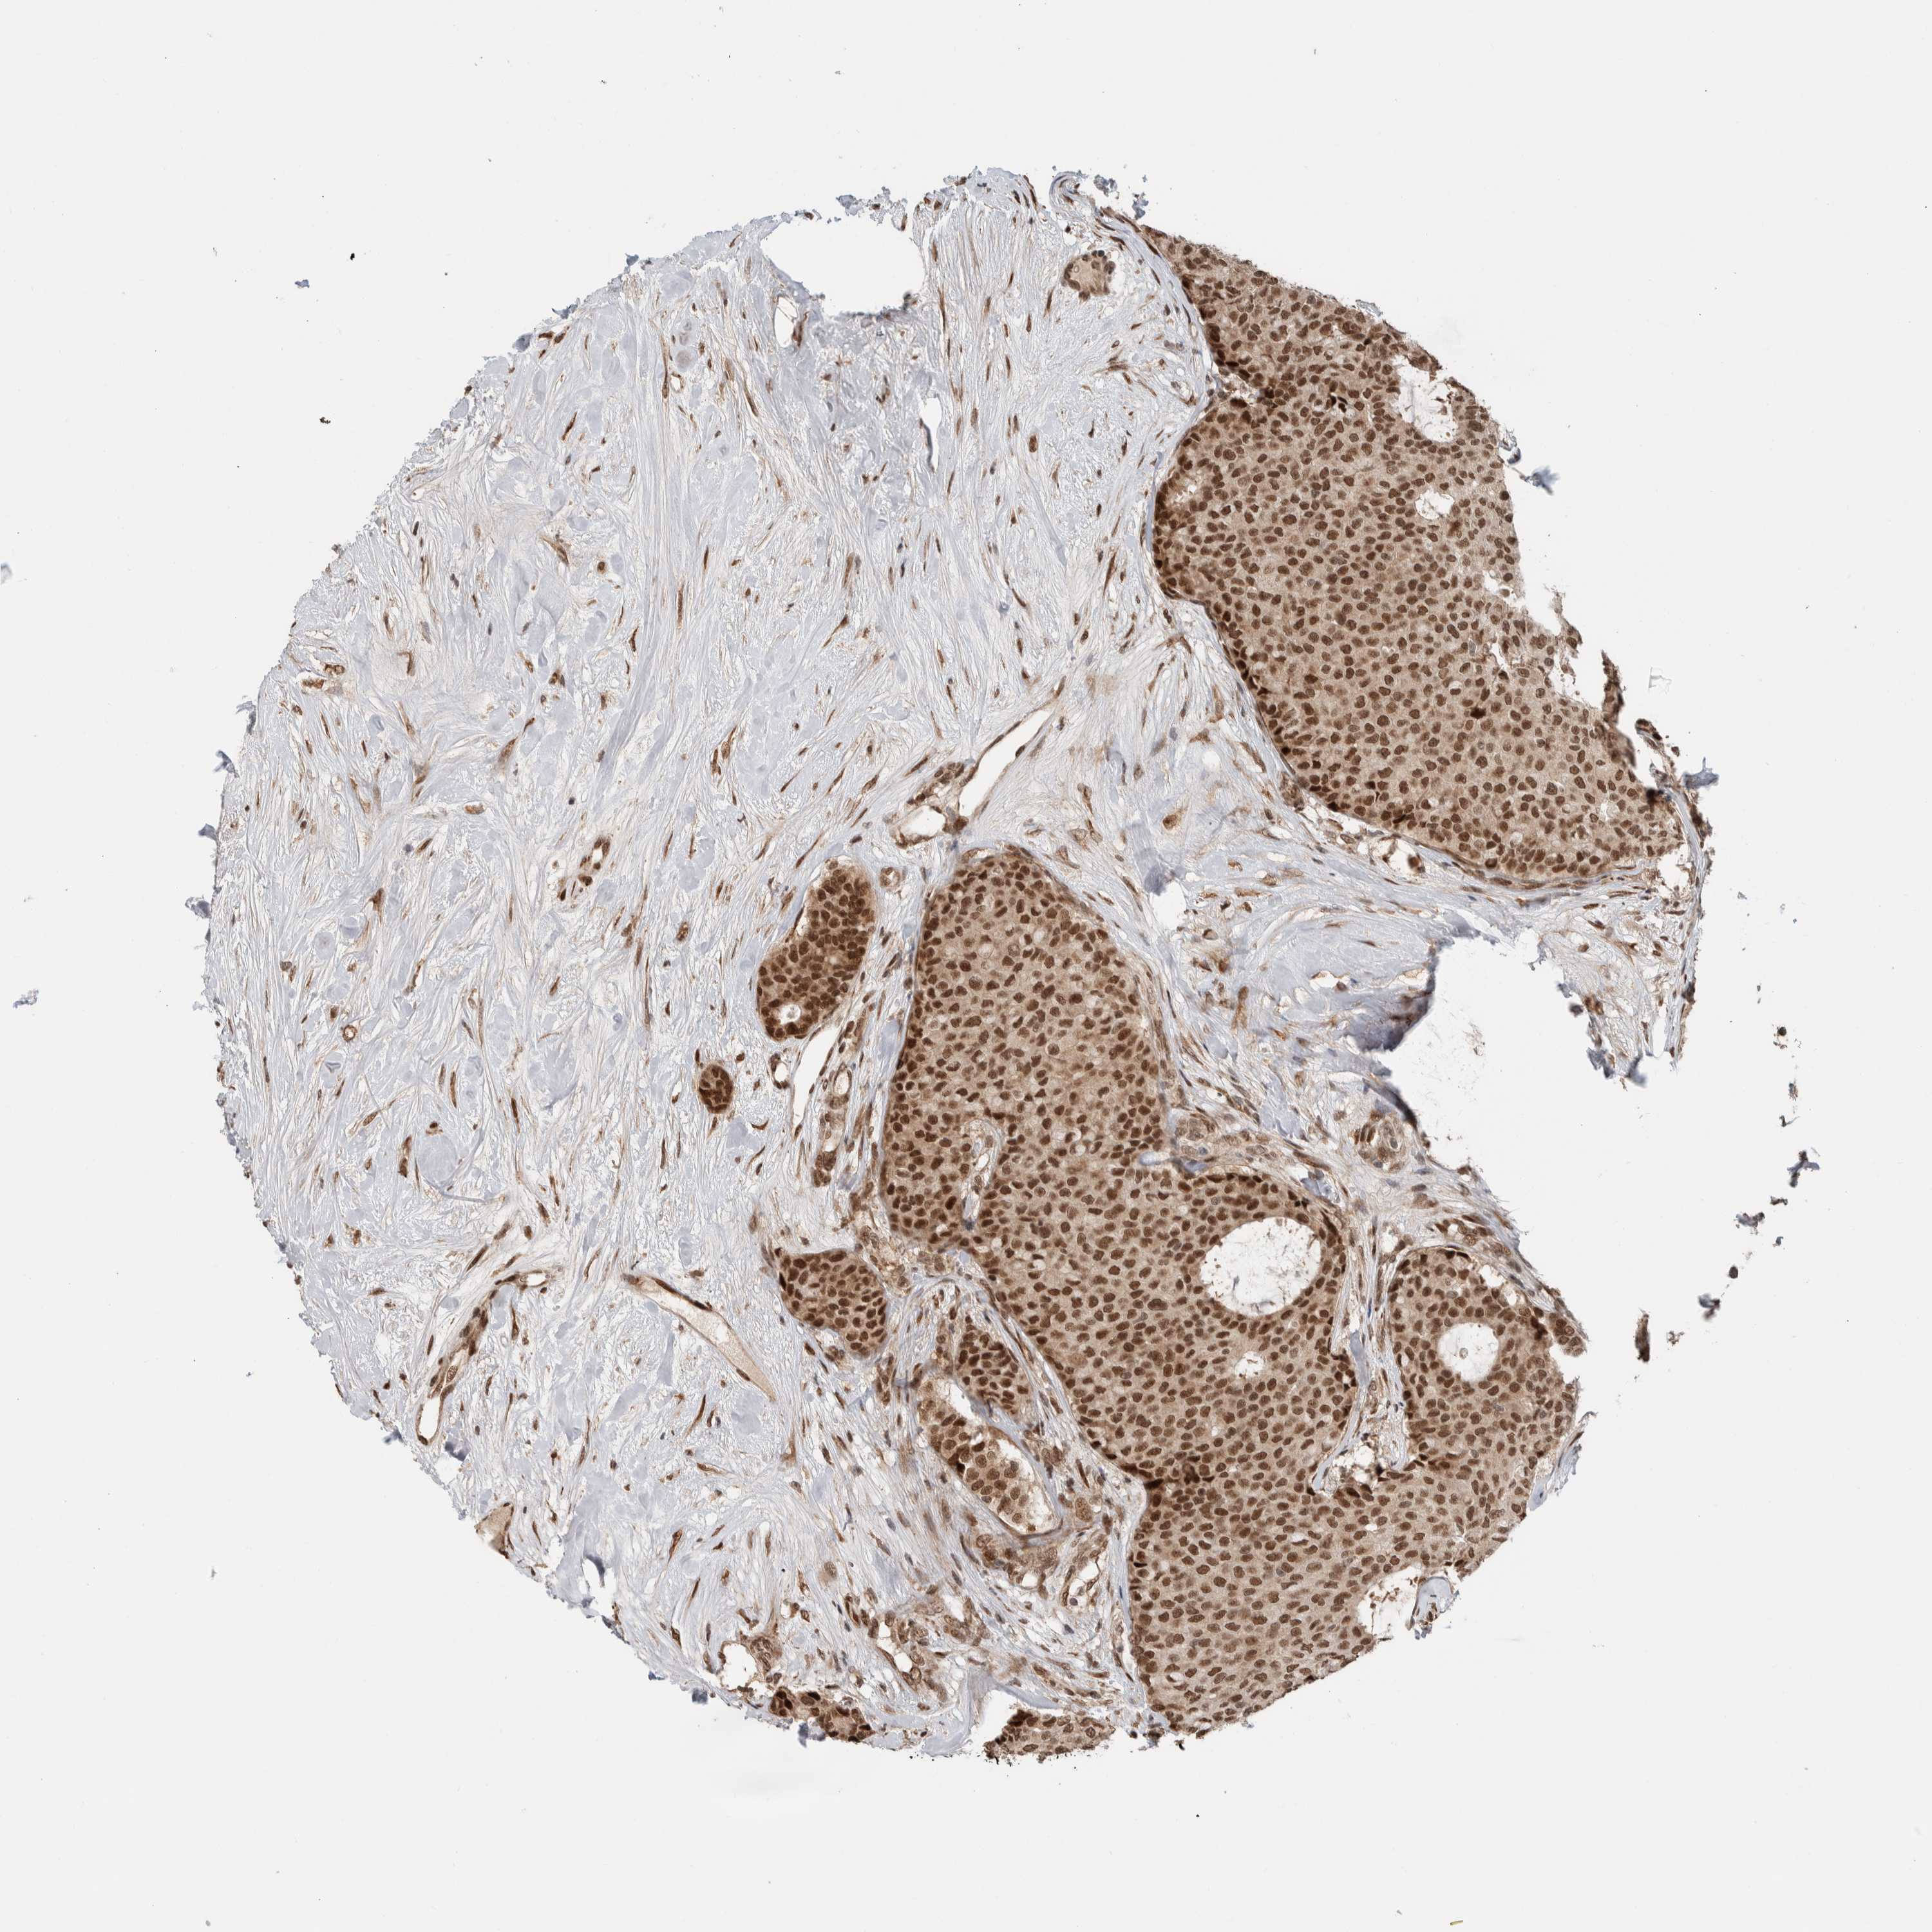

CANCER BREAST CANCER Show tissue menu

BRCA TCGA BRCA VALIDATION PROTEIN EXPRESSION